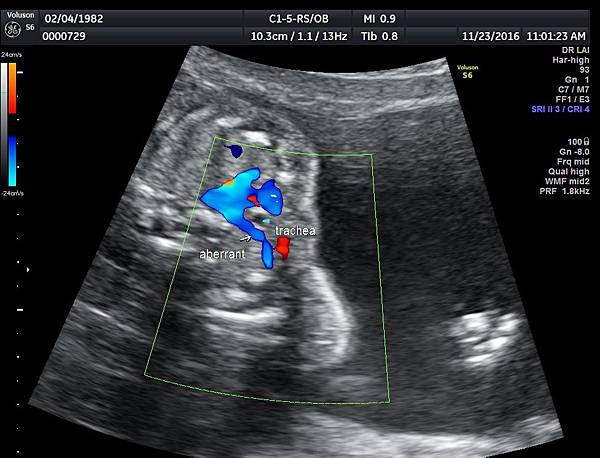

有一對夫妻因為我之前迷走性右側鎖骨下動脈(ARSA)的診斷而選擇孕兒診所,先生告知因為曾經有一個產前被我診斷ARSA的個案在他們醫院出生,他們花很久的時間才證實新生兒有ARSA,他覺得我很厲害,我有點不好意思,其實對專家而言,胎兒時期要診斷ARSA比新生兒容易,原因是胎兒時期超音波下,這條血管可以很清楚的被看到,它是從主動脈出來經過氣管的後面由左側繞到右側(附圖 1.),但是新生兒心臟超音波要看這條血管有困難,因為氣管擋住這條血管,醫師只能靠主動脈的第一個分支(brachiocephalic artery)沒有呈現 y 的特徵(附圖 2.),所謂 y 是brachiocephalic artery正常是會分出兩個分支(附圖 3.4.),一個是right common carotid artery,另一個是right subclavian artery,如果有迷走性右側鎖骨下動脈( ARSA ),就不會有正常的right subclavian artery,所以在新生兒的右頸部就不會看到 y的特徵,新生兒要直接看到迷走性右側鎖骨下動脈( ARSA)這條血管真的要花很多的時間(參考第51篇文章)。